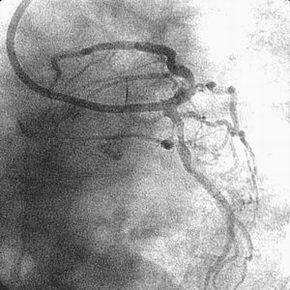

7F lTFA(Arrow金属シース55cm)で7F Mach1 CLS4.0を使用、#9→#6の順に1.5mm burr

でRotablatorを行ない、2.0mmへサイズアップしました。2.5mmバルーンで#9→#6と拡

張し、#6に3.5mm×23mmのCypherを留置しました。3.5mmバルーンで#6を高圧(最

大22ATM)後拡張し、#9の2.5mmバルーンとともにSimultaneous kissing inflationを

施行、#6、#9ともに良好な開大を得ました。

しかし、KBT直前の像(『ChoicePT2.GW.Prolapse』)では屈曲していただけの#9に挿

入したChoice PT2 LSが、KBT時像からは屈曲とともに先端1cm程度が断裂し

(『ChoicePT2.GW.Fracture』)、#9の末梢枝に遺残してしまいました

(『ChoicePT2.Fnl』2枚)。幸い虚血所見がまったくありませんでしたので手技は終

了とし、術後のCK逸脱もなし、翌日お元気に退院されました。

ステント留置の際にChoice PT2は#9から抜いておりましたし、strut越しの#9再選択

も容易でした。今回の手技に限ってはそれ以外もG.W.にムリな力が加わった機会はな

く、断裂の原因は現時点で不明です。私の印象からは、安全を意図してprolapseさせ

てあったChoice PT2の先端が小さな枝に補足され、U時の部分が心拍動とともに強い

屈曲をくり返されたために折れて断裂したように見えました。

Bostonからの速報では、先端から12mmあたりが切れていると考えられ、であればシェ

イピングリボンよりも手前のシャフトで断裂しているとのことです。USのデータで

は1万本に1本の割合で断裂が生じており、LSよりもMSで高頻度であるとのことでした。